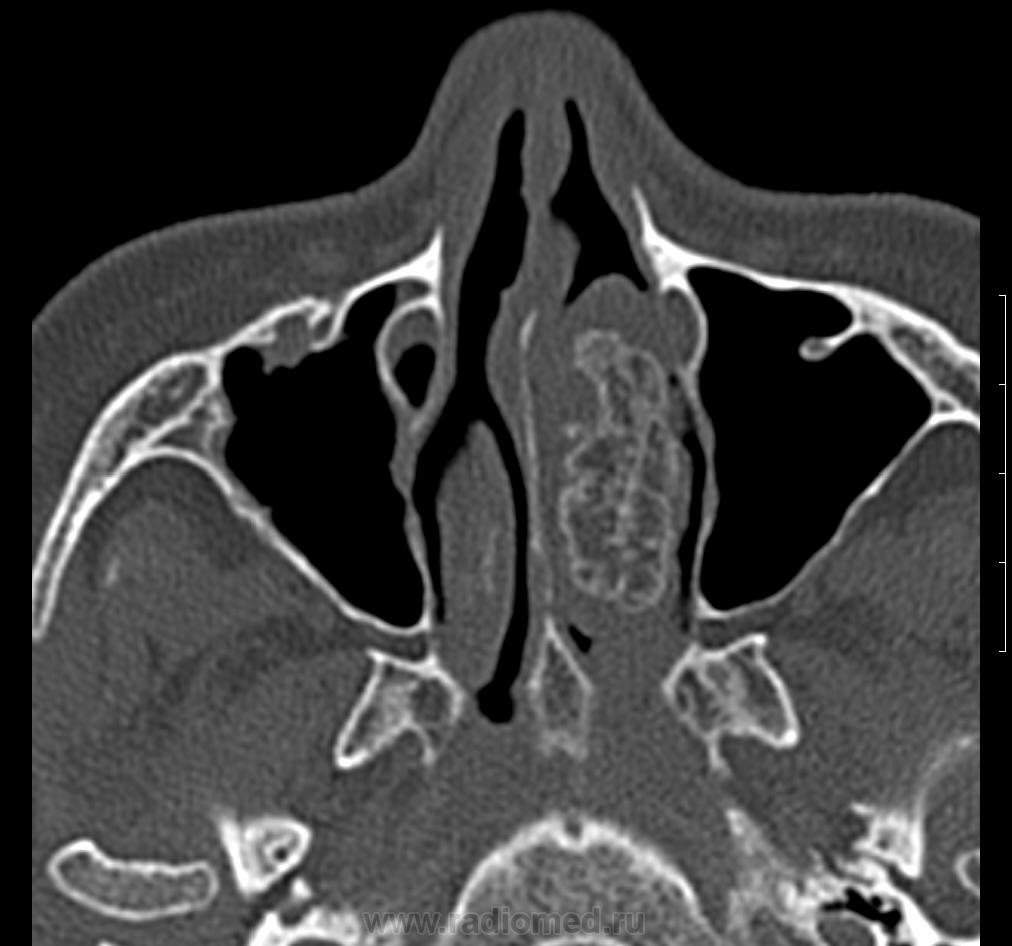

Женщина 1954г.р. обратилась к доктору 20.06.13г. с жалобами на головные боли, головокружение, тошноту. DS: энцефалопатия сложного генеза, ГБ, ШОХ. Отправлена МРТ г.м от 19.07.13г.- общая сообщающаяся гидроцефалия заместительного характера, TR клетках решетчатой кости, рекомендовано КТ. На приеме у ЛОР 26.0713г.: жалобы на затруднение носового духания; объективно- полипозная ткань в нос.пазухах слева. После проведенного КТ 30.07.13г. позвонил пациентке, говорит что примерно раз в три месяца бывают носовые кровотечения даже в горизонтальном положении. Что думаете коллеги?

Вот ее снимки.

Дополнительное образование в носовых раковинах слева ( или справа? у нас в МРТ это левая сторона ) с признаками обызвествления.Носовые раковины разрушены.Думаю, что точно нужно оперировать.

Левая сторона. Дело не в том, что нужна или нет операция. По моему это добро, но какое??? Хондромиксоидная фиброма? хондрома? Прилежащие костные и хрящевые структуры без признаков деструкции. У образования костно- хрящевая основа. Или я не в ту степь думаю...)